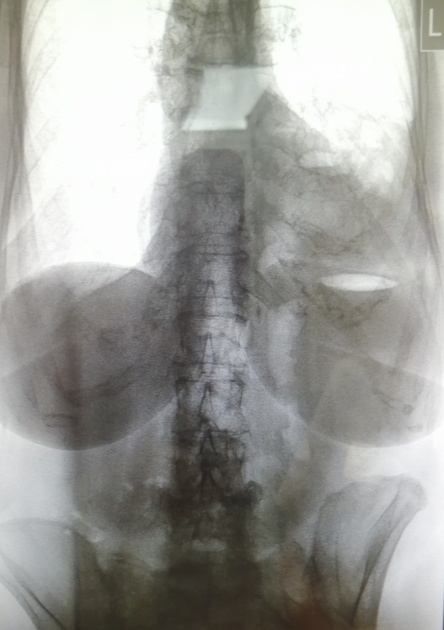

Мы решили представить один клинический случай неблагоприятного течения ГПОД. Больная Д., 79 лет, доставлена бригадой скорой медицинской помощи 02.01.2020 г. в приемное отделение ВМедА с жалобами на ноющие, распирающие боли, чувство тяжести в эпигастрии иррадиирующие в область сердца при употреблении пищи, изжогу, отрыжку тухлым воздухом, тошноту, неоднократную рвоту. Из анамнеза заболевания известно, что тошнота беспокоит больную в течение последних 3 нед, рвота появилась внезапно. Отмечает быстрое чувство насыщения после приема небольшого количества пищи. После приема спазмолитиков и самостоятельно вызванной рвоты боль стихает. Приступ боли длится примерно 1–1,5 ч, возникает 1–3 раза в день. Развитие и течение болезни: больная отмечает, что боли в эпигастрии беспокоят 10 лет. С декабря 2019 г. беспокоят вышеописанные жалобы. В октябре 2019 г. проходила лечение в хирургическом стационаре по поводу анемии. При обследовании обнаружены грыжа пищеводного отверстия диафрагмы IV степени, гипохромная анемия (рис. 4).

Рис. 4. Параэзофагеальная ГПОД (грудной желудок). Сдавление двенадцатиперстной кишки

Инструментальные методы исследования. Ультразвуковое исследование органов брюшной полости от 02.01.2020 г.: УЗ-признаки диффузных изменений печени по типу фиброза; полипы желчного пузыря; диффузные изменения поджелудочной железы; МКБ, камни и микролиты обеих почек; гастростаз. Видеогастродуоденоскопия от 05.01.2020 г.: кардия расположена на 34 см от резцов, определяется выраженная деформация просвета за счет смещенного желудка на 3/4 выше хиатального отверстия. В просвете большое количество застойного содержимого (более 1,0 л) и его отсутствие в антральном отделе. Выполнено заведение двухпросветного питательного зонда диаметром 12Fr до уровня связки Трейца. Тотальная параэзофагеальная грыжа. Эритематозная гастропатия. Деформация луковицы двенадцатиперстной кишки. Фунуция внешнего дыхания (ФВД) от 10.01.2020: ФВД сохранена. Жизненная емкость легких — нижняя граница нормы. Рентгенография желудка: нижняя 1/3 пищевода образует изгиб в грудной полости. Весь желудок, газовый пузырь расположен в грудной полости. Желудок заполнен контрастом по малой кривизне на задне-боковой стенке втяжения. Эвакуации контраста из желудка нет.